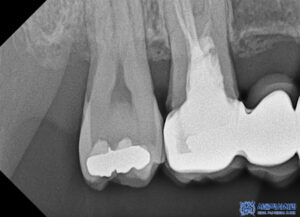

파노라마 촬영으로

전체 상태를 먼저 확인했습니다.

다만 크라운은 방사선 불투과성이 있어

내부 평가가 제한되므로,

정밀 엑스레이를 추가로 촬영해

보철물 하방 상태를 점검했습니다.

그 결과, 브릿지 아래쪽에

우식이 진행된 것이 확인되었습니다.